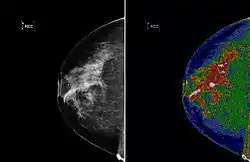

Область інтересів (англ. region of interest або ROI) — обрана підмножина зразків набору даних, визначена для конкретної мети[1]. Означена концепція зазвичай використовується у прикладних галузях. Наприклад, у рентгенології, межу пухлини можна визначити на зображенні, для визначення її розмірів. Ендокардіальну межу можна визначити на зображенні, можливо, на різних фазах серцевого циклу, наприклад кінцевої систоли та кінцевої діастоли, з метою оцінки функціонування серця. У географічній інформаційній системі (ГІС), ОІ можна прийняти буквально як багатокутну вибірку зa допомогою 2D карти. У комп'ютерному зорі й оптичному розпізнаванні символів, ОІ визначає межі об'єктів. У багатьох застосунках, символічні (текстові) позначки додаються в OI, для опису їх змісту більш компактним чином. OI може містити точки інтересу (POI, Points Of Interest).

Медична візуалізація

Медичні стандарти візуалізації, такі як DICOM містять загальні та специфічні для дослідження механізми для підтримки різних сценаріїв використання.

- Пікселі (можливо несуміжні), можуть бути класифіковані на сегменти, закодовані у об'єкти сегментації, або як бінарні чи ймовірнісні значення у растрі (який не повинен мати ту ж просторову вибірку або ступінь, як зображення, з якого була отримана сегментація); вони, зазвичай, посилаються на інші об'єкти, що містять структуровані дані (структуровані звіти).